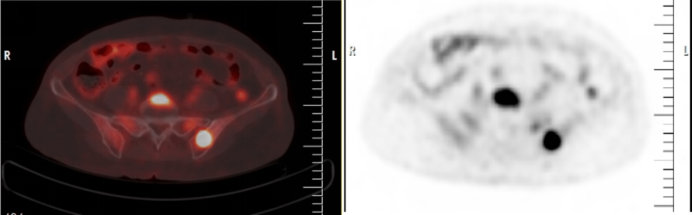

F-18 FDG-PET/CT顯示一名彌漫性大B細胞淋巴瘤患者的嗜FDG樣病變伴骨受累。圖片由Cureus通過CC BY 4.0提供。

為了闡明這一問題,研究小組比較了146例年齡在18-80歲的患者的回顧性數據,這些患者均經組織活檢確診為DLBCL。所有患者都進行了骨活檢,并接受了從顱底到大腿中部的全身F-18 FDG PET/CT掃描(Gemini TF 16,Philips)。

根據分析,47例(32.19%)在骨髓活檢中發現骨髓受累,50例(34.2%)在PET/CT掃描中發現骨髓受累。PET/CT有6個假陽性但活檢沒有,活檢有3個假陰性但PET/CT沒有。PET/CT的總體診斷準確率為93.84%。